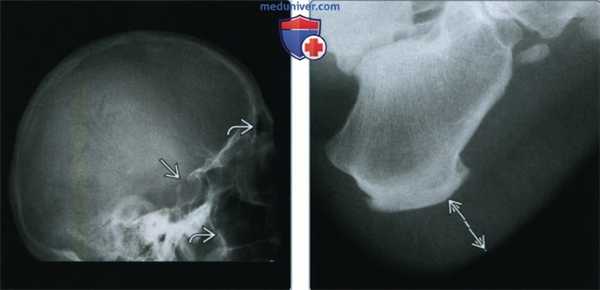

(Слева) Рентгенография костей черепа в боковой проекции: визуализируется увеличенное турецкое седло вследствие длительно существующей аденомы гипофиза, которая привела к ремоделированию. Увеличены околоносовые, особенно гайморовы пазухи. У этого пациента отмечается невыраженное утолщение костей черепа.

(Справа) Рентгенография стопы в боковой проекции: определяется разрастание мягких тканей. Утолщение мягких тканей в подпяточной области >2,3 см у мужчин и >2,15 см у женщин считается патологическим.